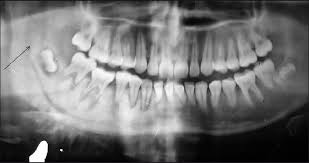

Mouth cancer starts in the cells lining the mouth. Moreover, the discoloring of the lining of the mouth may also be a sign of cancer. Cancer that arises from the jaw bone is termed primary jaw cancer. Although many jaw growths are benign, they can still do plenty of harm. Often, by the time a patient sees a doctor for a diagnosis, the tumor has grown into the neck. Gingiva cancer (also known as squamous cell carcinoma) is a progressive, rapid (weeks) local invasion of neoplastic epithelial cells within the oral cavity of dogs. Other conditions, like osteoporosis or arthritis, may also cause bone or joint pain. Although it's located in the front part of the mouth, it's actually considered a cancer of the head and neck. A canker sore looks like an ulcer, usually with a depression in the center. If a tumor spreads to the bone, it's called bone metastasis. A sore throat or persistent feeling that something is caught in the throat. This is known as a smoker's patch. Sneezing, difficulties in breathing, nose bleeds or other nasal discharges are common symptoms.

Picture of squamous cell carcinoma of the cheek Some of the signs are similar, including bleeding gums. Symptoms are similar to more typical osteosarcomas except that they may occur in very young children and are more widespread. Bone pain can cause a dull or deep ache in a bone or bone region (e.g., back, pelvis, legs, ribs, arms). It often causes changes in patches of skin, such as thick growths. Out of the various types of cancer, one is bone cancer which affects the. While a lump could be an infection or benign growth, these lumps could also be a sign that cancer is developing on the jawbone beneath the mouth's soft tissues. Some of the most common oral cancer symptoms and signs include: Cancer of the floor of mouth often looks like an ulcer and is painless. If a tumor near the jaw is hard to move when the doctor examines it, it often means that the cancer has grown into the jaw bone. A biopsy is the only way. Mouth cancer on your gums can sometimes be mistaken for gingivitis, a common gum inflammation. This aggressive type of cancer is more likely to spread to the lymph nodes

Taken by mouth or injection, they attack any cancer cells in the body. If the jaw bone looks normal on imaging tests and there's no evidence the cancer has spread there, the bone may not need to be cut all the way through. Jaw cancer results in pain in the area with difficulty in opening the mouth. Bone cancer is rare, making up less than 1 percent of all cancers. Lumps, swellings, fractures, joint tenderness and pain are some common symptoms of bone cancer in ankle and foot.

If a tumor near the jaw is hard to move when the doctor examines it, it often means that the cancer has grown into the jaw bone. Lumps, swellings, fractures, joint tenderness and pain are some common symptoms of bone cancer in ankle and foot. Bone pain can cause a dull or deep ache in a bone or bone region (e.g., back, pelvis, legs, ribs, arms). Other conditions, like osteoporosis or arthritis, may also cause bone or joint pain. A canker sore looks like an ulcer, usually with a depression in the center. As the cancer develops, though, the pain may become more persistent. Most cancer of the palate is squamous cell. The following are some mouth cancer pictures that can help you in knowing what does mouth cancer look like. Major signs that indicate bone cancer in foot and ankle. Leukoplakia (white and hardened patches) squamous cells is the name given to the flat cells that are present on the surface of the tongue, mouth and lips. If the jaw bone looks normal on imaging tests and there's no evidence the cancer has spread there, the bone may not need to be cut all the way through. This spread is called metastasis. Cancer that has started in one place can spread to and invade other parts of the body.